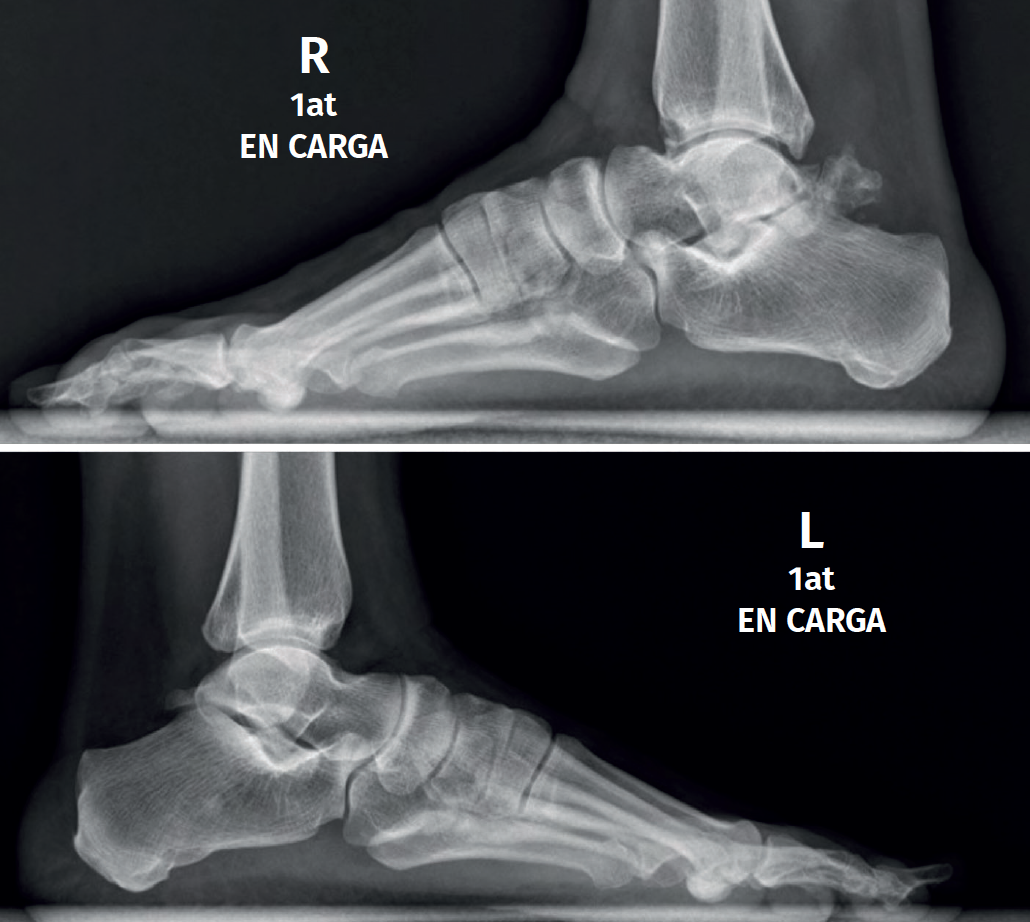

El os trigonum se presenta habitualmente de forma bilateral; puede alcanzar hasta 1,5 cm de diámetro (Figura 2) y presentarse dividido en 2 (os trigonum bipartitum). Cuando se fusiona al astrágalo se le denomina proceso trigonal y no es rara su presentación como os trigonum en un lado y proceso trigonal en el otro(4).

Se presentaría como una segmentación del astrágalo en el plano coronal con 2 fragmentos, uno anterior y otro posterior, separados por una hendidura o pseudoartrosis; a diferencia del os trigonum, el fragmento posterior se articula con la faceta articular posterior del calcáneo y en ocasiones también con la cara articular posterior de la tibia, pudiendo alcanzar un tamaño de un tercio o incluso más del volumen total (Figura 3); ambos fragmentos tendrían una estructura histológica similar(10).